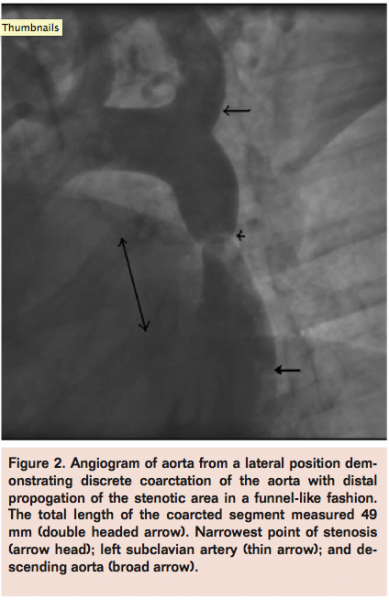

A 66-year-old female presented with a history of uncontrolled hypertension and shortness of breath. Initial transthoracic echocardiogram suggested a coarctation of her aorta and also revealed an unroofed coronary sinus. She underwent cardiac catheterization and angiography demonstrated a tight coarctation measuring 4 mm at its narrowest point (Figure 4). The coarcted segment extended 17 mm proximally and 26 mm distally to this point with a total length of 42 mm. A 34 mm covered CP stent was deployed over a 16 mm

BIB balloon through a 12 Fr sheath. This resulted in complete relief of the obstruction.

All patients demonstrated improved blood flow across that coarcted segment on post-procedural angiography (Figure 5).